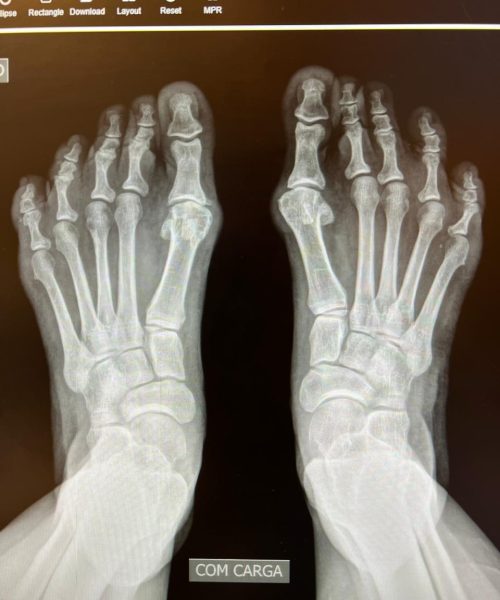

A cirurgia minimamente invasiva é uma abordagem cirúrgica que utiliza pequenas incisões e instrumentos especializados para tratar condições no pé e tornozelo, minimizando danos aos tecidos circundantes.

A cirurgia minimamente invasiva é indicada para pacientes que buscam uma recuperação mais rápida e menos desconforto pós-operatório. É especialmente benéfica para casos selecionados de deformidades e lesões nos pés e tornozelos. de alguma condição que afeta a articulação do tornozelo, como lesões de cartilagem, inflamações, corpos livres, impactos, instabilidade ou artrose .

A cirurgia é realizada através de pequenas incisões, geralmente com o auxílio de um endoscópio. Isso permite ao cirurgião tratar a condição alvo com precisão, reduzindo o trauma aos tecidos circundantes.